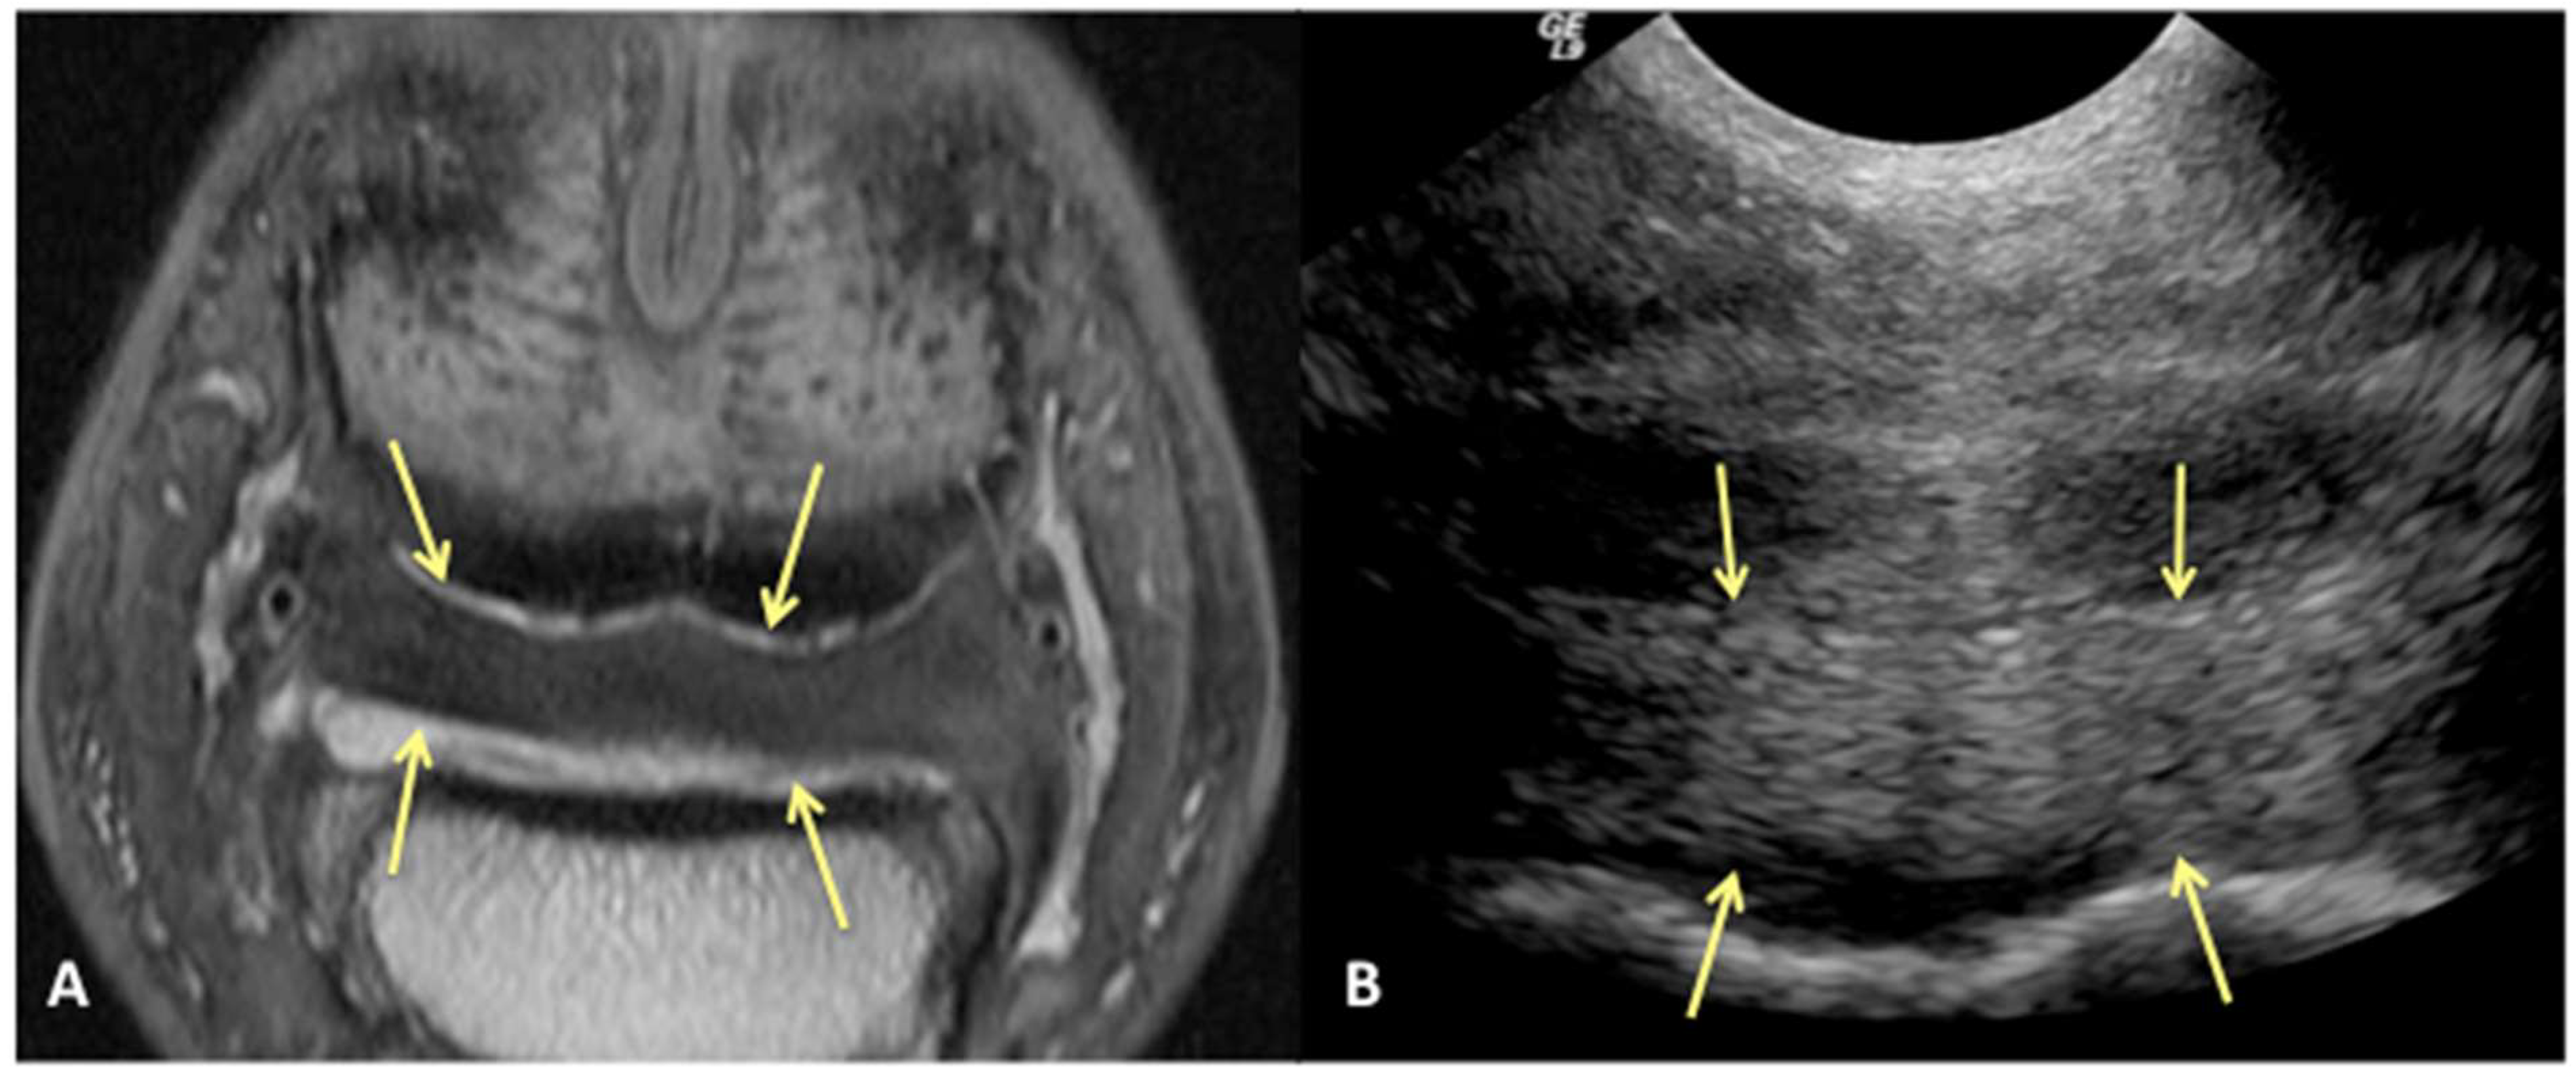

We can reject the other part of our hypothesis that ultrasound will under-diagnose the amount of injury to the DDFT. While ultrasound was good for evaluating the dorsal surface tearing of the DDFT at the level of the navicular bursa, with a sensitivity of 85%, it had a lower specificity of 60%. This lower specificity indicates that we could have less ability to truly rule in a lesion of the DDFT as diagnosed by ultrasound. Of the 43/70 limbs that did not have evidence of DDFT dorsal surface tearing on MRI, 17 were over-diagnosed as having tearing or bulging of the dorsal surface on ultrasound (Figure 4). This was a surprising finding, in part because the authors tend to be conservative in their assessment of the DDFT in this location. However, imaging the navicular bursa and DDFT within the hoof capsule is limited by probe position and angle of incidence. On and off-angle imaging cannot be used to help distinguish the borders of objects located distally within the hoof capsule, and drop-out artifacts can artifactually enhance the appearance of DDFT lobe enlargement. Additionally, although the researchers are trained to be as objective as possible, there is likely some degree of unconscious bias towards suspecting abnormalities when performing an ultrasound on a horse diagnosed with pain originating from the digit.

Figure 4. Transverse proton dense MR image (A) and corresponding ultrasound image (B) at the level of the collateral sesamoidean ligament and proximal recess of the navicular bone. Dorsal bulging and tearing was identified on ultrasound in the lateral lobe, white arrow heads; however, the DDFT is normal on MRI (yellow arrows). Palmar is on the top of the image, dorsal is on the bottom of the image, lateral is on the left.